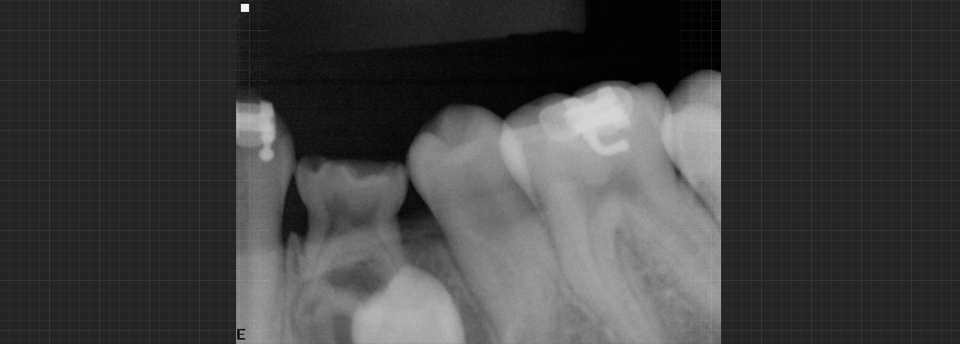

We enjoy working with children of all ages and feel it is very important to begin dental health early. Our patients are 3 years and up. Many dental problems can be intercepted and treated easily if diagnosed early. Our office offers sealants, fillings, crowns, extractions on “baby” teeth and adult teeth. We offer screening for future orthodontic treatment and have a wonderful team of specialists to help make difficult cases easy. Click here to find out more.